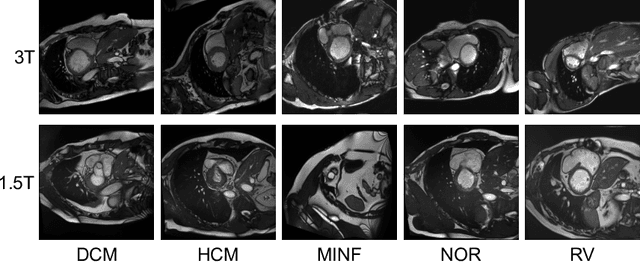

In the era of deep learning, aggregation of data from several sources is considered as a common approach to ensuring data diversity. Let us consider a scenario where several providers contribute data to a consortium for the joint development of a classification model (hereafter the target model), but, now one of the providers decides to leave. The provider requests that their data (hereafter the query dataset) be removed from the databases but also that the model `forgets' their data. In this paper, for the first time, we want to address the challenging question of whether data have been forgotten by a model. We assume knowledge of the query dataset and the distribution of a model's output activations. We establish statistical methods that compare the outputs of the target with outputs of models trained with different datasets. We evaluate our approach on several benchmark datasets (MNIST, CIFAR-10 and SVHN) and on a cardiac pathology diagnosis task using data from the Automated Cardiac Diagnosis Challenge (ACDC). We hope to encourage investigations on what information a model retains and inspire extensions in more complex settings.